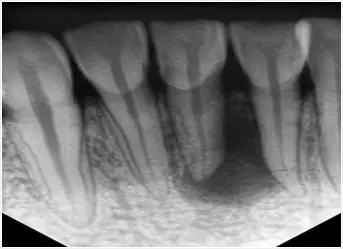

牙片

3、有既往病史或者是藥物過敏等情況的**,建議戴上之前的病曆診斷報告、片子等檢查結果,如果有拍牙片,也可以帶著,能用上的話還能減少診療時間。